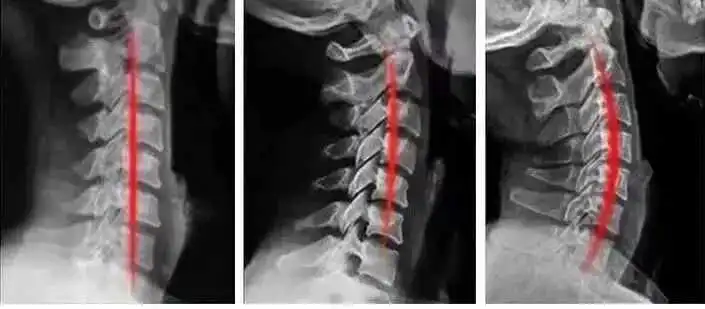

长时间睡这款0压枕,对我们的头、肩、颈都是非常友好的,甚至还可以帮助我们恢复健康的生理曲线!

坚持用下来,惊喜的发现,颈椎在慢慢恢复健康的生理曲线!